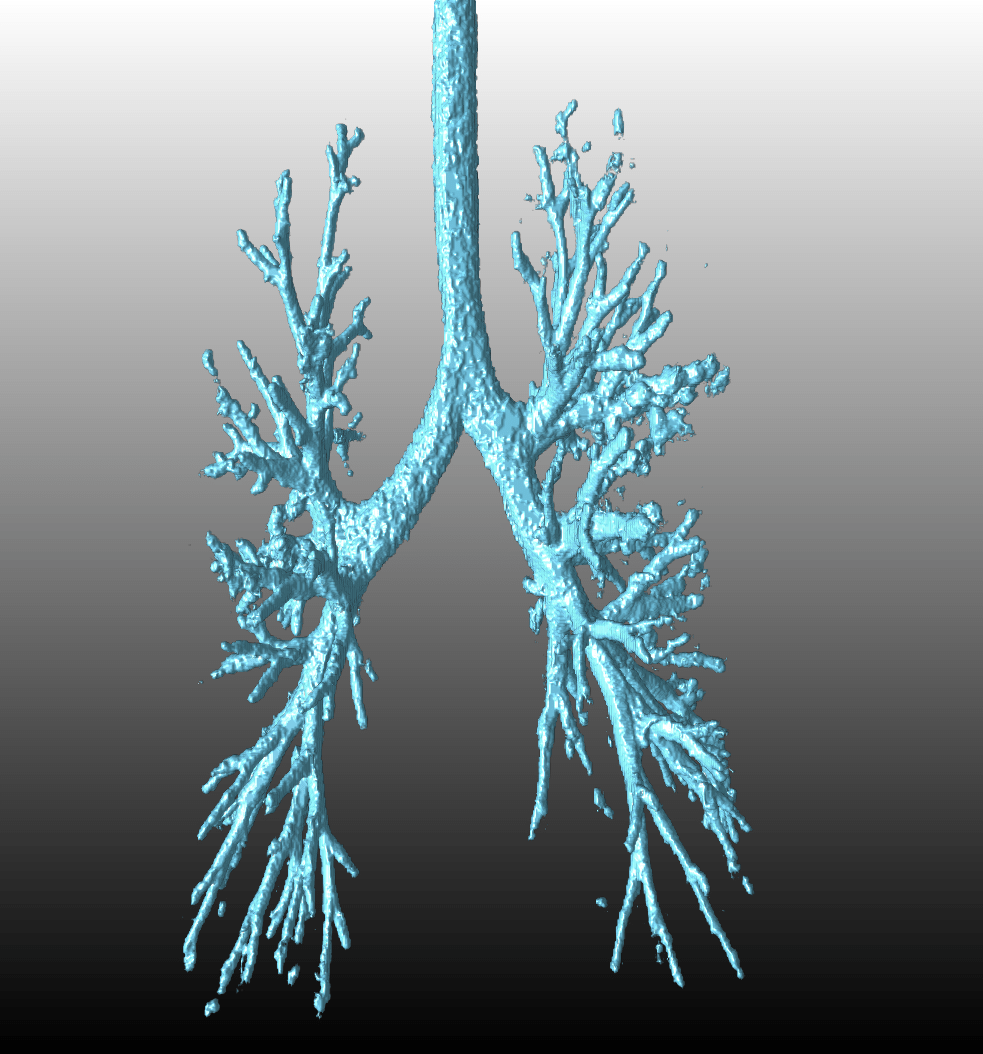

[Uncaptioned image]

Automated airway segmentation by learning graphical structure

In this research project, we put forward an advanced method for airway segmentation based on the existent convolutional neural network (CNN) and graph neural network (GNN). The method is originated from the vessel segmentation, but we ameliorate it and enable the novel model to perform better for datasets from computed tomography (CT) scans. Current methods for airway segmentation are considering the regular grid only. No matter what the detailed model is, including the 3-dimensional CNN or 2-dimensional CNN in three directions, the overall graph structures are not taken into consideration. In our model, with the neighbourhoods of airway taken into account, the graph structure is incorporated and the segmentation of airways are improved compared with the traditional CNN methods. We perform experiments on the chest CT scans, where the ground truth segmentation labels are produced manually. The proposed model shows that compared with the CNN-only method, the combination of CNN and GNN has a better performance in that the bronchi in the chest CT scans can be detected in most cases. In addition, the model we propose has a wide extension since the architecture is also utilitarian in fulfilling similar aims in other datasets. Hence, the state-of-the-art model is of great significance and highly applicable in our daily lives.

Trachea is one of the crucial organs in the human respiratory system. The diagnosis of many diseases such as idiopathic pulmonary fibrosis (IPF) depends on the observation of main trachea and bronchus.

In the contemporary society, computed tomography (CT) is one vital tool for the visualisation and evaluation of lung diseases [6]. Clinicians mainly rely on manual inspection of chest CTs to recognize the airways, which is time-consuming and even in some cases inaccurate. Therefore, the computer-assisted methods are necessary to be developed over the years to diagnose the lung fibrosis and measure the severity. For instance, axial CT scans are overlaid with different colours by CALIPER (Computer-Aided Lung Informatics for Pathology Evaluation and Rating software) in order to measure the IPF severity [7]. In this example, CALIPER is one tool for visualising and comparing reticulation of lungs. Besides, healthy human airway and airway with IPF differ in the airway branch structures [17]. Clinicians are able to observe the tracheae from CT scans and give the possible diagnosis of patients.

We are aware of the significance of the computer-assisted techniques, so in this thesis, we are aimed to explore the segmentation of airways from chest CT scans, which is one of the key processes to the final automated diagnosis.